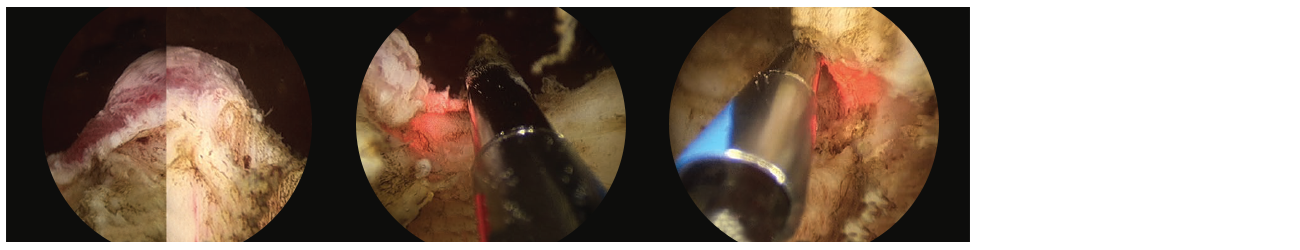

• Next, I vaporize a working space and demarcate the apex adjacent to the verumontanum. (Fig. 1)

2 scope images. Identifying anatomical landmarks (image shows left ureteral orifice). Figure 1: Demarcation of apical limits in front of veru.

• Thereafter, I create deepened and widened groves from the bladder neck to the verumontanum at the 5 o’clock and 7 o’clock positions. (Fig. 2)

3 scope images. Identifying how to vaporize a working space. Figure 2: Groove creation at 7 o’clock down to capsule.